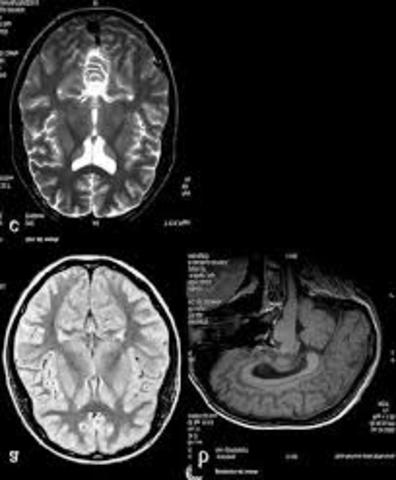

• Resonancia magnética

Resonancia magnética

En 1990, Seiji Ogawa, demostró en estudios con animales que una zona que contiene gran cantidad de hemoglobina desoxigenada deforma ligeramente el campo magnético que rodea al vaso sanguíneo, deformación que se ve reflejada en una imagen por resonancia magnética.

en 1992 otros investigadores como John W. Belliveau del Massachusetts, implementaron la RM en humanos para guiar las cirugías de cerebro sin correr el riesgo de dañar otras partes del mismo.